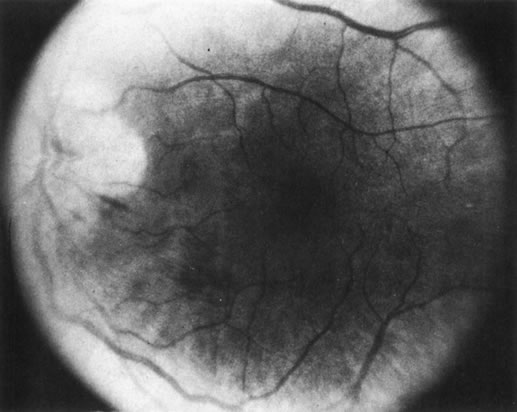

Necrotic melanomas account for approximately 5% of uveal melanomas; in the majority of cases, there is intraocular inflammation accompanying the cataract.7–9Figures 1 and 2 demonstrate a typical case. The patient had a long history of unilateral decreased vision. The eye had become painful 1 month before admission, and he was referred for evaluation of uveitis. Clinically, there was a dense, unilateral cataract with significant intraocular inflammation, which was manifested as a ciliary flush with 2+ cells and flare. Media opacity obscured all fundus detail. An immersion B-scan demonstrated a large intraocular tumor that was most consistent with a uveal melanoma. The eye was removed, and the diagnosis was confirmed histologically.10

Fig. 1. A unilateral media opacity in an adult, requiring that either a foreign body or an intraocular tumor be ruled out. The finding of a large episcleral (“sentinel”) vessel was consistent with either an intraocular tumor or an inflammation. An immersion B-scan helped determine the diagnosis (see Fig. 2).